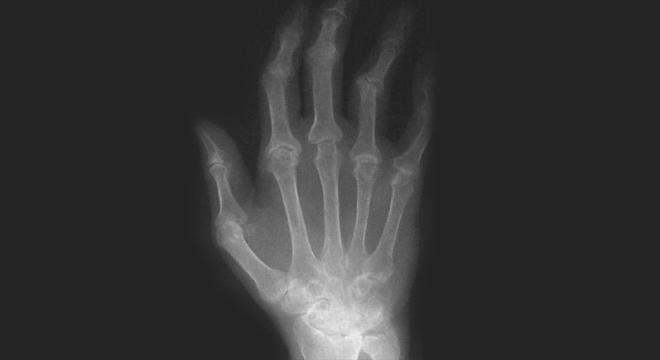

Rheuma: Deformationen im Röntgenbild

Die entzündungsbedingten Gelenkschäden der RA sind irreversibel. Sie treten rascher auf als früher aufgrund von Untersuchungen mit herkömmlichen Röntgen-Aufnahmen vermutet worden ist. Die Diagnose ist deswegen so rasch wie möglich zu stellen.

• In späteren Stadien Deformationen des Skeletts, vor allem der Finger

Ist anfänglich nur das Bindegewebe der Gelenksinnenhaut (Synovium) betroffen, schreitet die Entzündung und Zerstörung ohne wirksame Behandlung weiter und ruiniert Knorpel, Sehnen und Knochen. Die betroffenen Gelenke werden funktionsunfähig und weisen aufgrund der Zerstörung der Sehnen oft groteske Fehlstellungen auf.

Jedes Gelenk kann befallen werden. Normalerweise sind beide Körperhälften symmetrisch betroffen. Häufig betroffen sind die Fingergrundgelenke, Handgelenke, Fingermittelgelenke, Zehengrundgelenke, Schultergelenke, Kniegelenke, Sprunggelenke und Ellbogen.